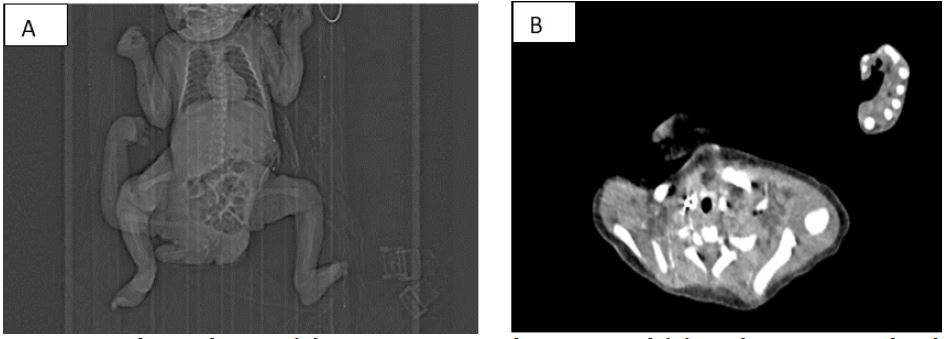

Initial investigations revealed an omphalocele, a left colostomy for neonatal colonic perforation, and exstrophy of the bladder. MRI and CT imaging showed that the parasite contained five vertebrae, two ribs, a complete right lower limb with pelvic bone, a partial upper limb with hemiscapula, and a functional kidney and bladder system. Vascularization was derived from both internal iliac arteries of the autosite. The anteroposterior infantogram and the bony axial scan clearly illustrated the parasitic structures and vertebral segment (Figure 1).

Figure 1: Image scanographique showing (A) anteroposterior infantogram and (B) axial CT scan revealing bony parasitic structures.